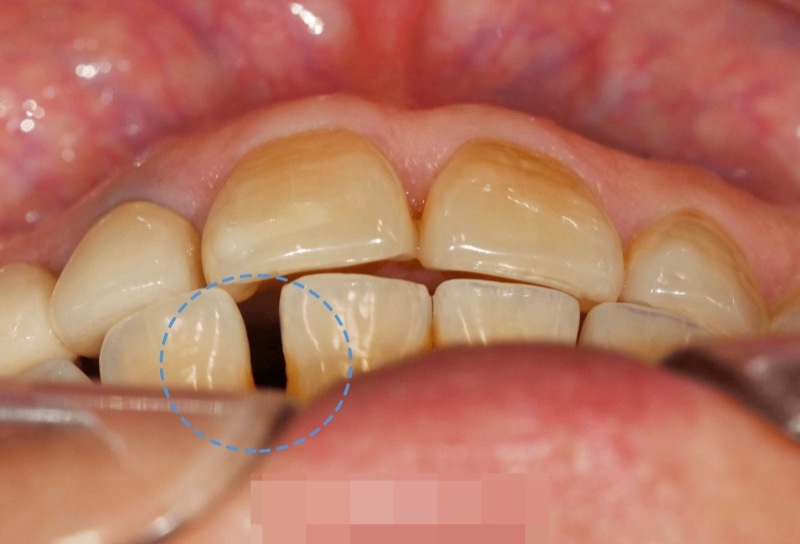

하악 전치부의 간격에 의하여

Space가 눈에 띄게 도드라집니다.

특히 41번과 42번에서의 간격이

넓은 편이었기에 진행되는 과정을 파악해

기간을 결정해야 될 것으로 사료됩니다.

진단이 이뤄졌다면 하악 전치부 6개,

33번부터 43번에 해당하는 치아에

브라켓을 붙이는 과정을 선행합니다.

물론 42번과 43번의 간극을

메꿔줘야 되기에

좀 더 힘을 주고 움직여야 되는데요.